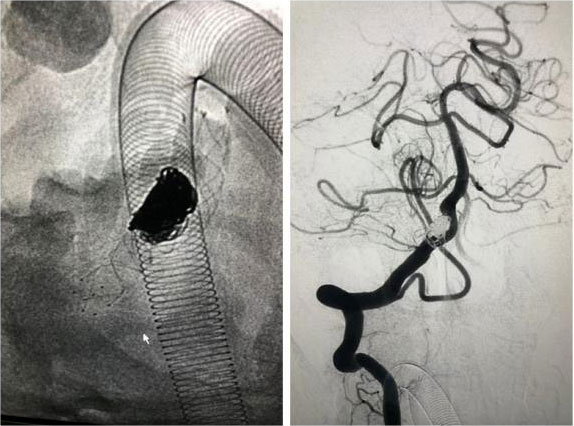

動脈瘤栓塞術(shù):

只需要在病人大腿根部開個小切口,用一根纖細的微導(dǎo)管經(jīng)血管抵達所要治療的動脈瘤部位,向動脈瘤內(nèi)堵塞非常精細的彈簧圈,達到很好治療動脈瘤的目的。是微創(chuàng)外科的方法之一。

▲ 一位動脈瘤患者術(shù)前影像

▲ 術(shù)后,造影顯示動脈瘤無顯影,栓塞成功